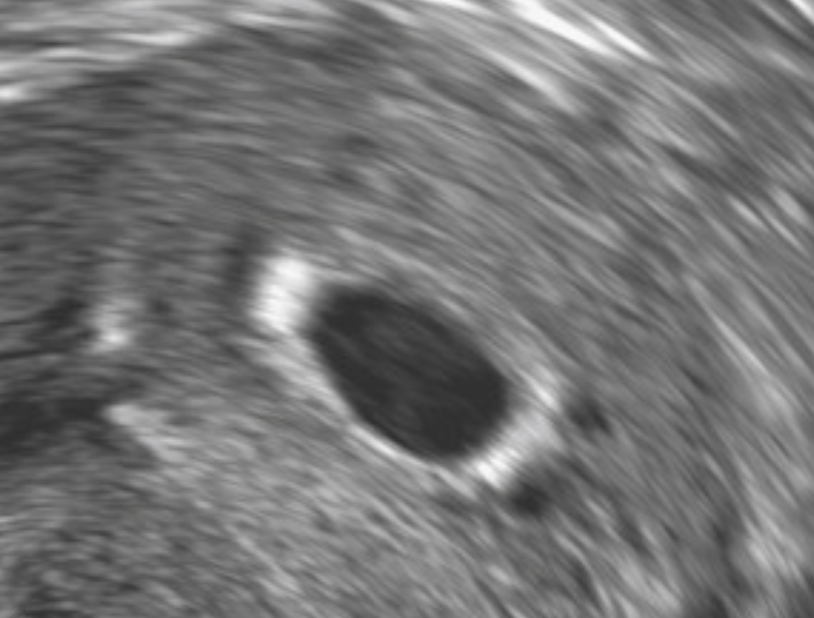

A 7-week gestation sac (black circle) containing a yolk sac (smaller, brighter circle) and embryo